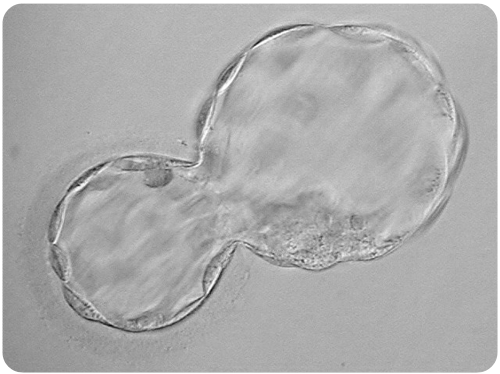

The picture below shows an advanced stage of blastocyst development. Notice the central fluid-filled cavity. The cells within the blastocyst have already differentiated into the inner cell mass (at seven o’clock) that will give rise to the fetus and the trophectoderm cells that will form the future placenta.

At this stage, the embryos are still microscopic, invisible to the naked eye.